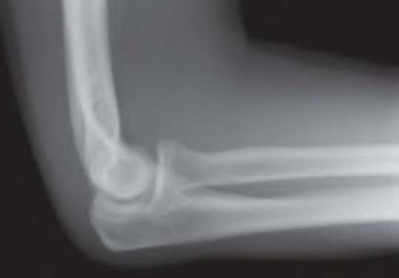

A 35-year-old woman reports wrist pain after a fall onto an outstretched hand. On exam, she has focal tenderness over the wrist snuffbox. A radiograph and CT image are shown in Figures A and B. What is the proper treatment of her injury?